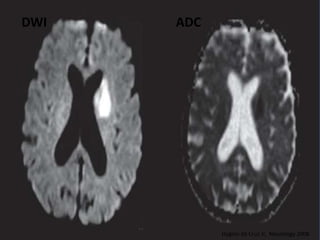

DWI

• Bright regions – decreased

water diffusion

• Dark regions – increased

www.radiopaedia.org

DWI ADC

Hygino da Cruz Jr, Neurology 2008